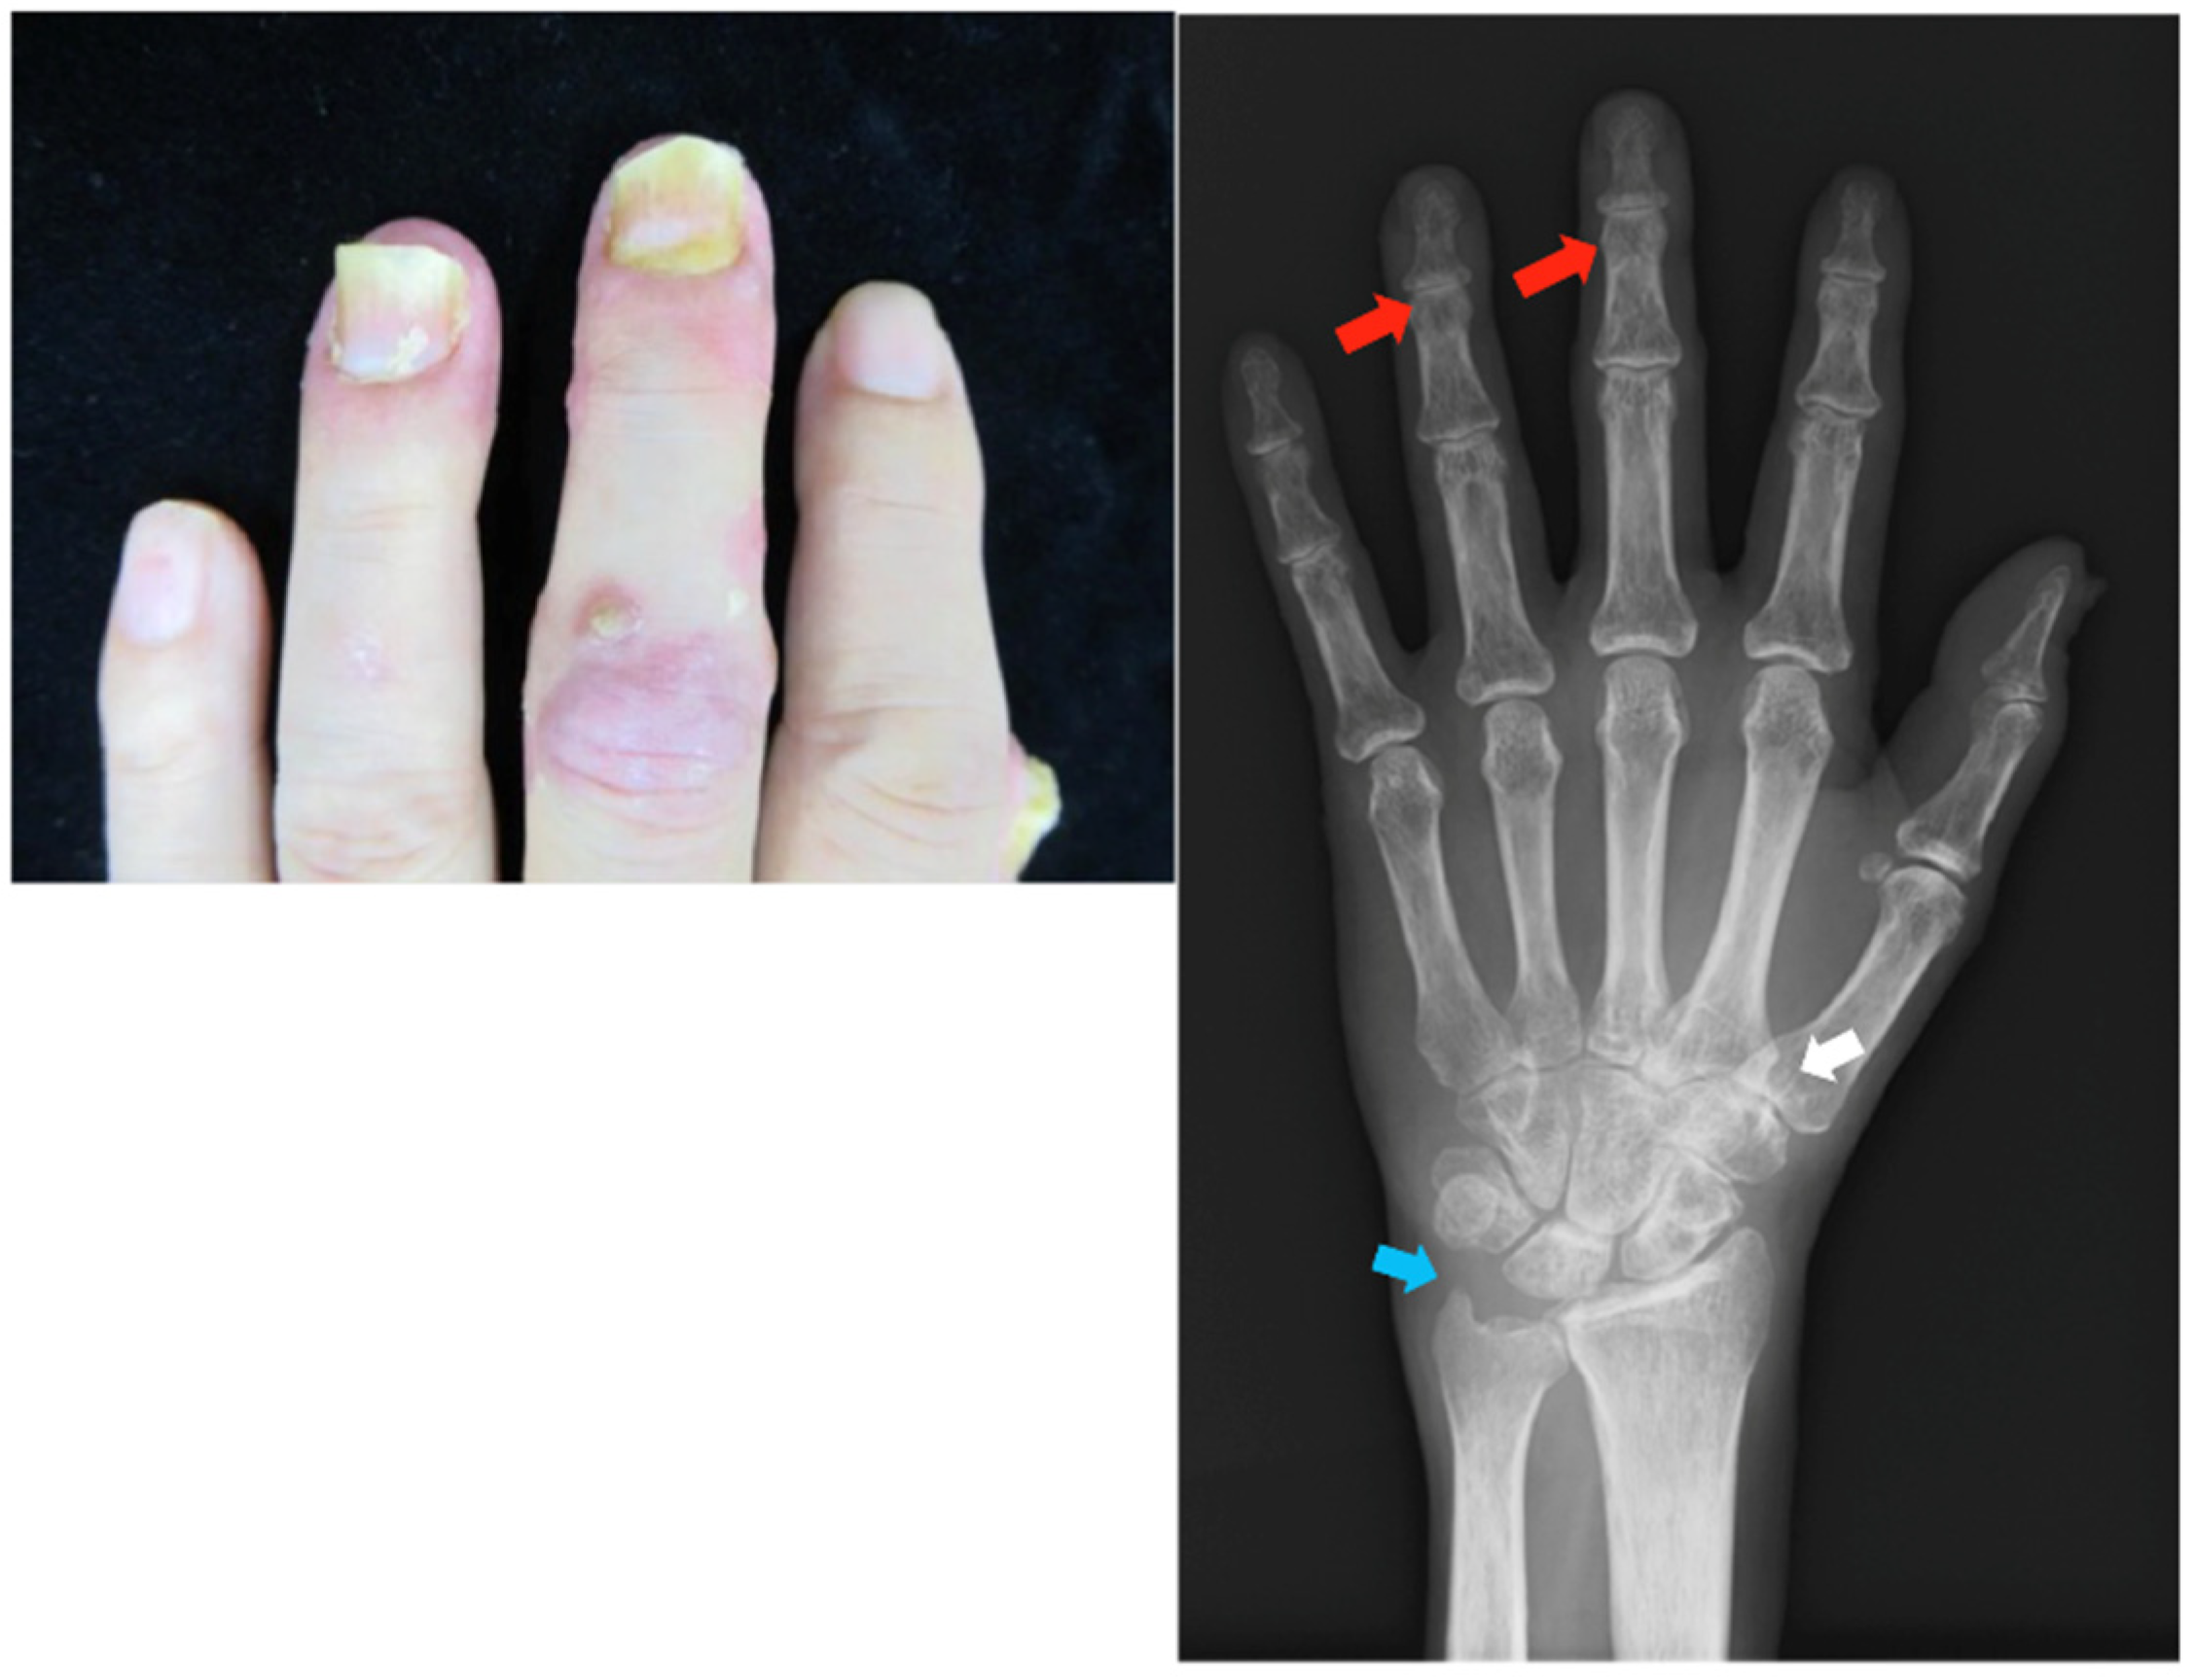

Patient: Woman in her 60s

Patient: Man in his 50s